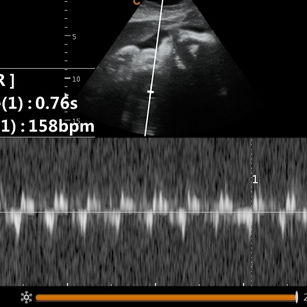

Lungs: Almost fully developed but still fine-tuning- babies born now may sometimes need a little help with breathing.

At 36 weeks, your baby looks very much like a newborn but is still maturing—especially the brain and lungs. Another week or two inside helps ensure they’re fully ready for life outside.